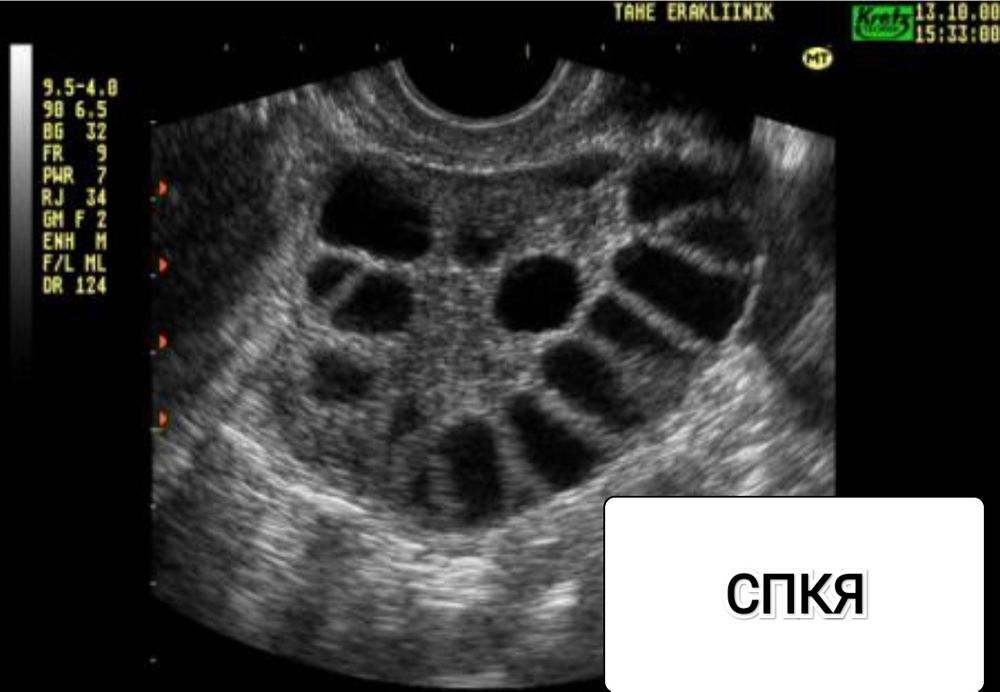

Немного покопавшись в интернете, я нашла четкое сравнение этих диагнозов. Но, что больше всего мне понравилось - сравнение УЗИ. Сопоставив все факты (фото приложу ниже) и своё УЗИ я наконец поняла - тут, кажется, ярко выраженные МФЯ. Не понимаю, зачем было только запугивать все это время тем что " с таким то диагнозом, попробуйте и родить... это будет чудо "🤦♀️🤷♀️

СПКЯ - это синдром, который ставят, если имеются 2 из 3 критериев: олиго- или ановуляции, гиперандрогения, классическая картина расположения фолликулов по строме в виде ожерелья на УЗИ.

МФЯ - это просто количество антральных фолликулов >15-20.

Соответственно, если у Вас есть ановуляции/олигоовуляции и гиперандрогения, то картина УЗИ уже не важна. А если есть только множество фолликулов на УЗИ, то никакого СПКЯ у Вас нет.